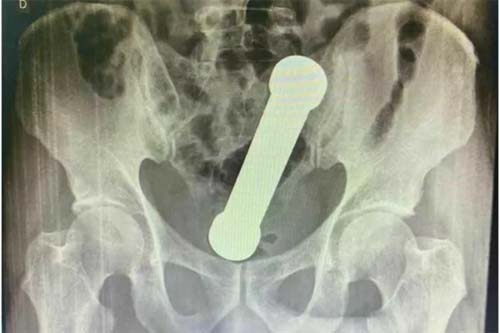

Após exames físicos, foram solicitados hemograma, estudo bioquímico e radiografia da região abdominal. A radiografia apresentou a presença de um corpo estranho em forma de haltere de ginástica em "localização aproximada na transição retossigmóide" — entre a parte terminal do intestino e parte inicial do reto. “Devido ao quadro clínico estável do paciente, sem sinais de perfuração, optou-se pela abordagem retal inicial”, relatou a publicação.